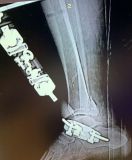

3. Intra-articular fracture of the left distal tibia associated with lateral malleolar fracture in a 33-year-old female.

Treatment: 1st step, external fixation. 2nd step, after 14 days removal external fixation and at the same time open reduction internal fixation (ORIF)

I. Before surgery II. 1st step, the external fixator III. 2nd step, removal the external fixator and at the same time (ORIF)